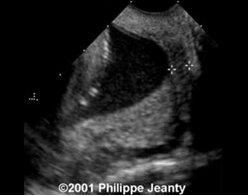

- Chọn mặt cắt dọc qua kênh CTC sao cho thấy được biểu mô ống cổ tử cung (nhận biết bằng hình ảnh các tuyến của kênh CTC) và cả lỗ trong lẫn lỗ ngoài của cổ tử cung.

- Lỗ trong CTC tạo thành đỉnh một tam giác cân có hai cạnh là mép trên và mép dưới CTC nằm sát lỗ trong.

- Chiều dài kênh CTC: từ lỗ trong CTC (nơi kênh CTC tiếp xúc với túi ối) tới lỗ ngoài cổ tử cung.